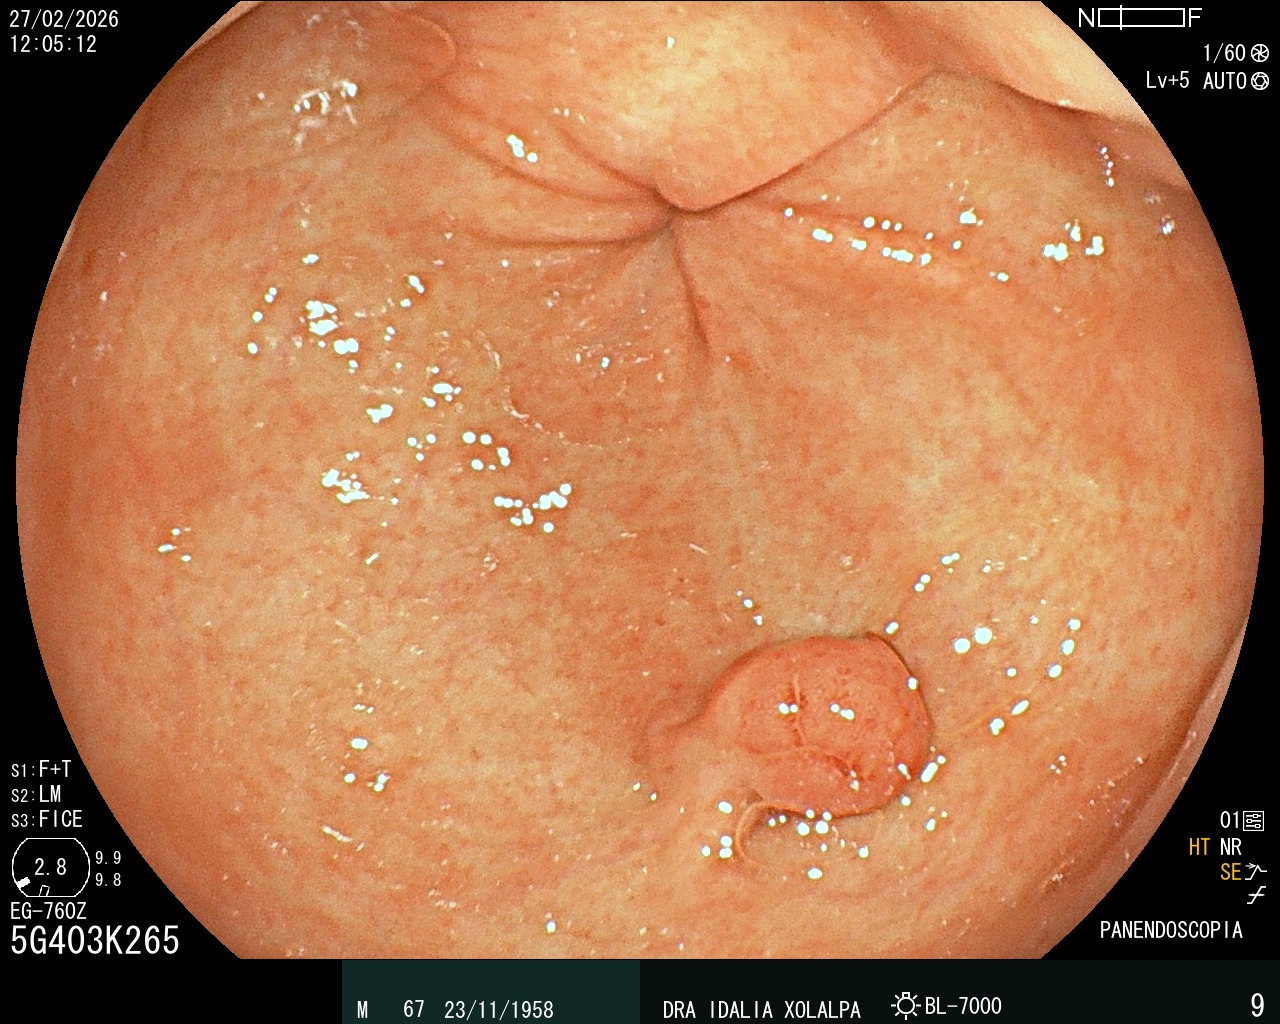

Pólipo en Antro

Hallazgo de pólipo en antro gástrico